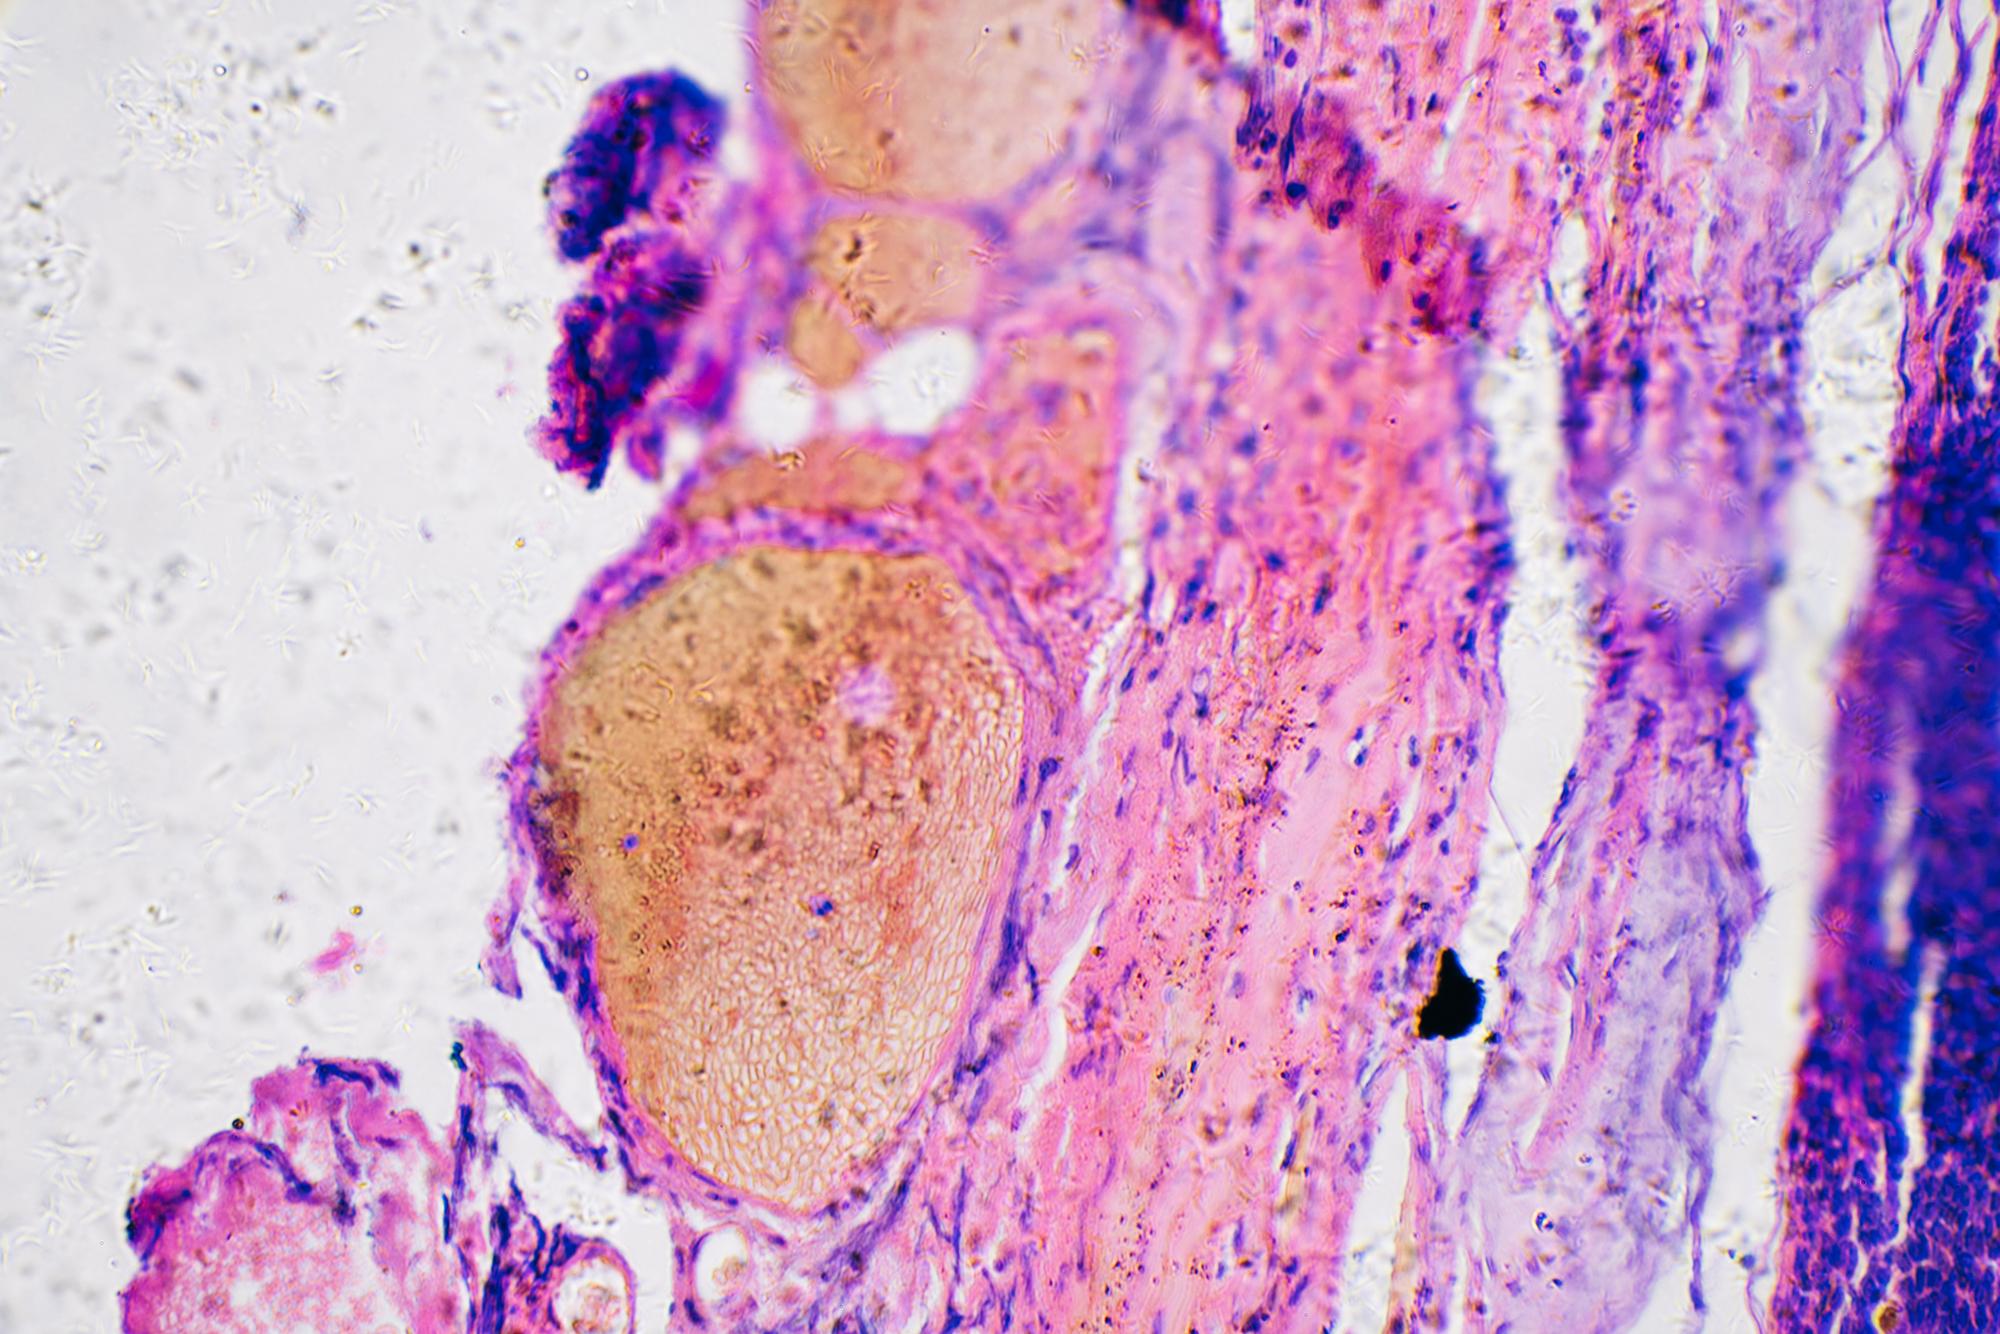

Melanoma cancer cells of human under microscope

#02  La chronothérapie ou soigner à la bonne heure

Notre horloge interne, le rythme circadien, agit sur le système immunitaire et le comportement des cellules tumorales. Des études appliquées aux cancers suggèrent qu'il faudrait adapter l'heure de prise des médicaments pour augmenter leur efficacité